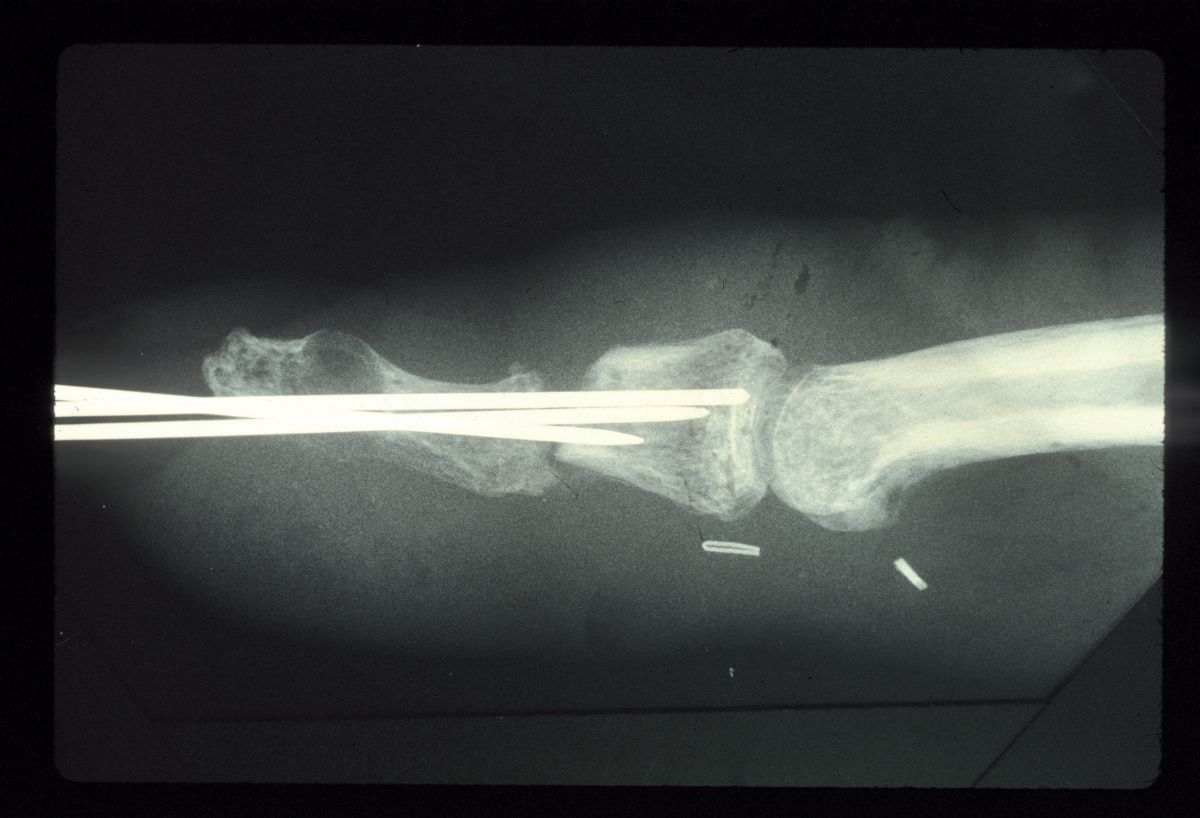

| Intraoperative films. |

| Graft in place. Exposure facilitated by using 25 gauge needles to convert a Heiss to a Gelpi retractor. |